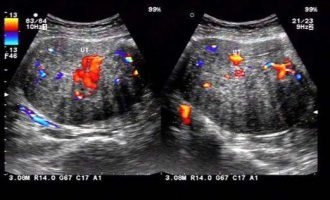

對于許多備孕中的女性,尤其是計劃通過輔助生殖技術(shù)(如試管嬰兒)實現(xiàn)生育的夫.婦而言,卵巢功能是決定成功率的關(guān)鍵因素之一。卵巢不僅負(fù)責(zé)排卵,還分泌雌激素和孕激素,

.對于許多渴望生育的女性而言,卵巢功能是決定生育能力的關(guān)鍵因素之一。當(dāng)被診斷為“卵巢功能不好”時,很多備孕女性會感到焦慮和迷茫,尤其是當(dāng)自然受孕困難時,試管嬰兒